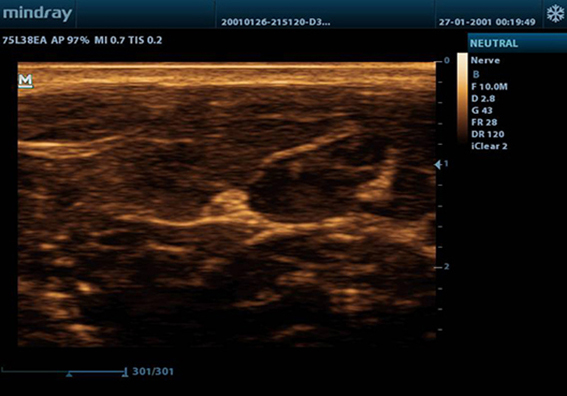

B-SteerTM

Alat untuk biopsi yang lebih dalam: memungkinkan pengaturan garis pemindaian untuk mendapatkan visibilitas yang lebih baik dari jarum, saraf dan pembuluh kecil.